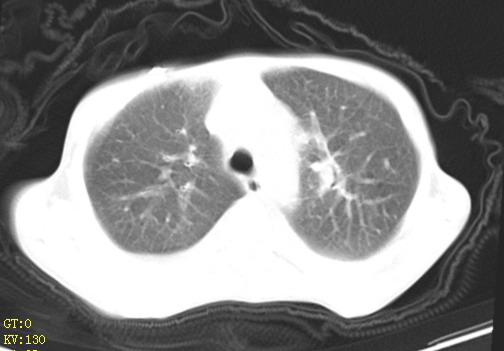

女,12岁,气促、咳嗽2天,3个月前查胸片示:两肺感染,急诊入院查ct,血常规等未检查。

双肺中下野不规则片絮状阴影,中外带明显,双侧胸腔少量积液,心影增大,心腔密度减低,隆突下及左侧气管旁见钙化淋巴结影,考虑双肺感染、心衰;建议结合临床除外h1n1并急性心衰,先心不能排除。

两肺多发片絮状模糊影,以下肺外带居多,内见支气管气像,纵膈窗未减影,两侧胸腔积液,心影增大,结合心超,支持重症肺炎,非常时期,甲型h1n1流感不排除。

1)考虑两肺感染性病变;建议抗炎治疗后复查。2)双侧少量胸腔积液。